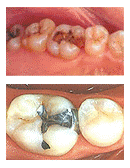

아말감 치료

아말감은 은과 주석의 합금에 수은을 섞어서 굳게 하는 재료로 전통적으로 가장 많이 쓰인 재료입니다.

보통 은으로 때웠다고 할 때나, 검은색 재료로 때웠다고 할 때는 이것을 말하는 것입니다.

의료보험 혜택이 있어 비용이 저렴하고 진료 방법이 간단하며 너무 크지 않은 대부분의 충치 치료를

할때 많이 사용했으나 보기에 좋지 못하고 수은의 사용 때문에 찬반의 논란이 많습니다.